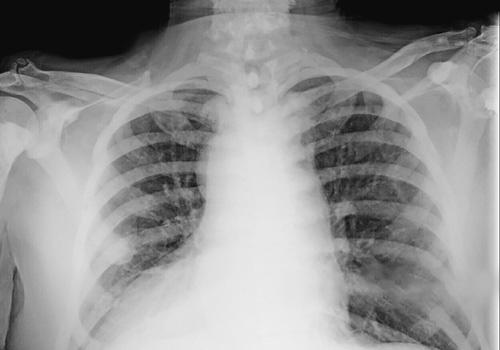

We describe the case of a male Caucasian patient with SIT and aortic dissection type A, who occurred to our Emergency Department with a severe clinical condition of shock. Using the fast diagnostic approach with chest X-Ray and echocardiography followed by computed tomography investigation, a Standford type A acute aortic dissection and the presence of SIT were detected. The patient was subjected to surgical treatment with optimal results in a short time.

我们描述了一名患有SIT和A型主动脉夹层的男性白种人患者的病例,该患者因严重休克状态被送至我们的急诊科。采用胸部X线和超声心动图的快速诊断方法,随后进行计算机断层扫描检查,检测出A型急性主动脉夹层和SIT的存在。患者接受了手术治疗,短期内取得了最佳效果。